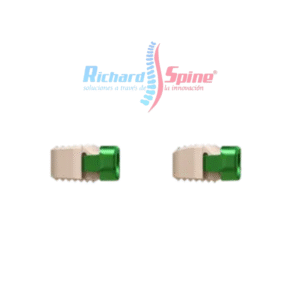

Malla de Titanio para Columna Cervical

- La malla de titanio está disponible en diferentes alturas para cada patología y condiciones anatómicas. arquitectura abierta para malla de titanio permite la fusión ósea y optimiza el crecimiento óseo y sus anillos extremos paralelos para restaurar la alineación espinal normal y resistir el hundimiento. mientras tanto, se utiliza malla de titanio para Trauma, tumor, espondilolistesis, disco degenerativo enfermedad.